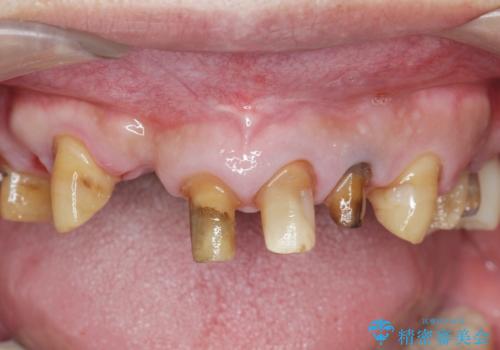

歯周病治療を伴う前歯審美セラミック治療

- 前歯の見た目をなんとかしたい、とセラミック治療を希望され来院されました。

セラミック治療を行う前に歯周病の問題を解決すべく歯周外科を行い歯周ポケットを除去し整備したのちセラミックブリッジ・クラウンの製作を行います。